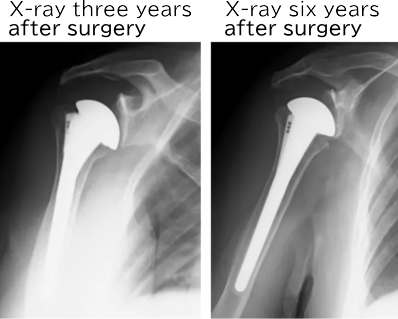

3 years after surgery

The allograft remains fixed to the humerus even after 3 years, and the stem is firmly secured within the humerus.

Symptoms 3 years after surgery

・There is no shoulder pain.

・It is difficult to move the hand behind the back.

・Life is much easier compared to before the surgery.